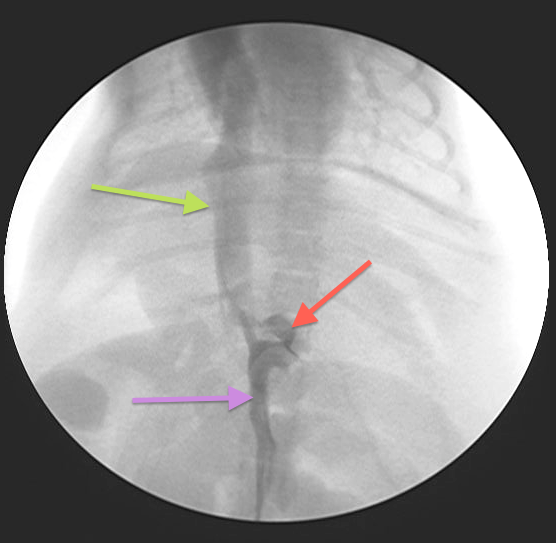

Intraoperative fluoroscopy is used to confirm the presence of a shunt

Fig 2: PSS surgery is performed using intraoperative fluoroscopy

The shunt is identified (Fig 3) and a test ligation performed to confirm identification of the correct vessel and to assess whether or not the patient can tolerate complete ligation of the shunt (Figs 4-5)

Fig 3:

Intraoperative fluoroscopy (portovenogram) showing the same PSS as in Fig 1: Purple arrow = Portal vein; Green arrow = CVC; Red arrow = PSS